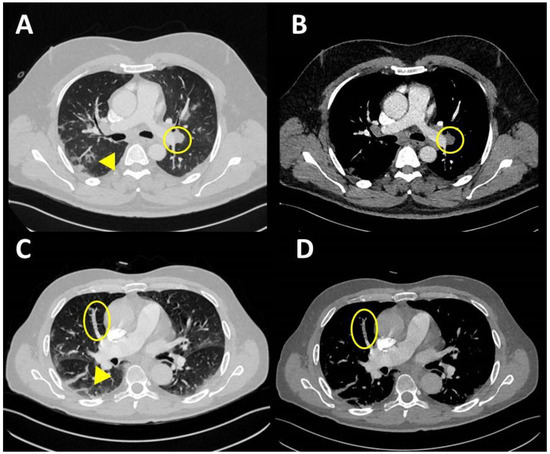

- Pontone, G.; Scafuri, S.; Mancini, M.E.; Agalbato, C.; Guglielmo, M.; Baggiano, A.; Muscogiuri, G.; Fusini, L.; Andreini, D.; Mushtaq, S.; et al. Role of computed tomography in COVID-19. J. Cardiovasc. Comput. Tomogr. 2021, 15, 27–36. [Google Scholar] [CrossRef]

- Martínez Chamorro, E.; Revilla Ostolaza, T.Y.; Pérez Núñez, M.; Borruel Nacenta, S.; Cruz-Conde Rodríguez-Guerra, C.; Ibáñez Sanz, L. Tromboembolismo pulmonar en pacientes con COVID-19: Estudio de prevalencia en un hospital terciario. Radiologia 2021, 63, 13–21. [Google Scholar] [CrossRef]

- Léonard-Lorant, I.; Delabranche, X.; Séverac, F.; Helms, J.; Pauzet, C.; Collange, O.; Schneider, F.; Labani, A.; Bilbault, P.; Molière, S.; et al. Acute pulmonary embolism in patients with COVID-19 at CT angiography and relationship to d-dimer levels. Radiology 2020, 296, E189–E191. [Google Scholar] [CrossRef] [PubMed] [Green Version]

- Poyiadji, N.; Cormier, P.; Patel, P.Y.; Hadied, M.O.; Bhargava, P.; Khanna, K.; Nadig, J.; Keimig, T.; Spizarny, D.; Reeser, N.; et al. Acute pulmonary embolism and COVID-19. Radiology 2020, 297, E335–E338. [Google Scholar] [CrossRef]

- Helms, J.; Tacquard, C.; Severac, F.; Leonard-Lorant, I.; Ohana, M.; Delabranche, X.; Merdji, H.; Clere-Jehl, R.; Schenck, M.; Fagot Gandet, F.; et al. High risk of thrombosis in patients with severe SARS-CoV-2 infection: A multicenter prospective cohort study. Intensive Care Med. 2020, 46, 1089–1098. [Google Scholar] [CrossRef] [PubMed]

- Loffi, M.; Regazzoni, V.; Toselli, M.; Cereda, A.; Palmisano, A.; Vignale, D.; Moroni, F.; Pontone, G.; Andreini, D.; Mancini, E.M.; et al. Incidence and characterization of acute pulmonary embolism in patients with SARSCoV-2 pneumonia: A multicenter Italian experience. PLoS ONE 2021, 16, e0245565. [Google Scholar] [CrossRef] [PubMed]

- Grillet, F.; Behr, J.; Calame, P.; Aubry, S.; Delabrousse, E. Acute Pulmonary Embolism Associated with COVID-19 Pneumonia Detected with Pulmonary CT Angiography. Radiology 2020, 296, E186–E188. [Google Scholar] [CrossRef] [PubMed] [Green Version]

- Meiler, S.; Hamer, O.W.; Schaible, J.; Zeman, F.; Zorger, N.; Kleine, H.; Rennert, J.; Stroszczynski, C.; Poschenrieder, F. Computed tomography characterization and outcome evaluation of COVID-19 pneumonia complicated by venous thromboembolism. PLoS ONE 2020, 15, e0242475. [Google Scholar] [CrossRef]